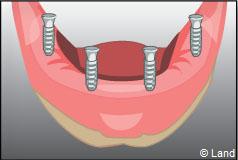

Les implants peuvent aussi servir à stabiliser un appareil amovible au maxillaire supérieur comme au maxillaire inférieur. Dans ce cas, les implants retiennent la prothèse amovible par des systèmes d’attachement.

Deux techniques sont possibles. Elles font appel à la barre de rétention ou aux boutons-pressions.

Exemple d’une réhabilitation complète implantaire

Situation clinique terminée